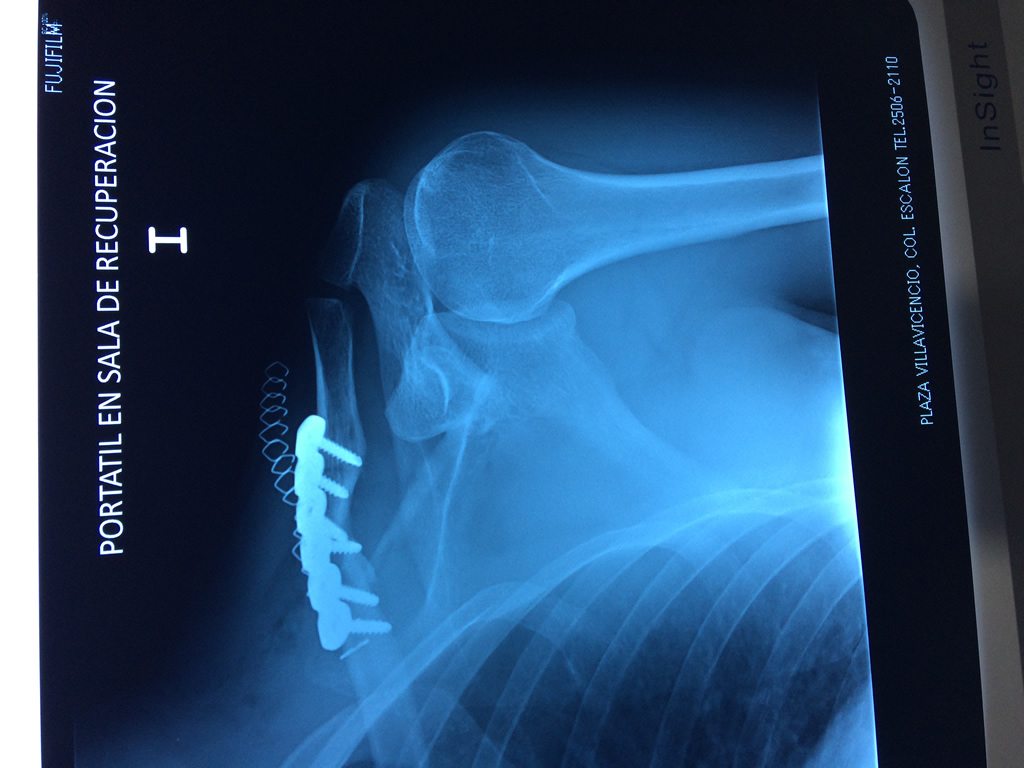

Cirugías de Hombros - Clavícula

La clavícula es un hueso largo, con forma de "S" itálica, situado en la parte anterosuperior del tórax. Junto con la escápula forman la cintura escapular. Se puede palpar por toda su longitud y se extiende del esternón al acromion de la escápula, siguiendo una dirección oblicua lateral y posterior.

Se considera el único medio de unión entre el miembro superior y el tórax. A pesar de su aspecto, similar al de un hueso largo, posee una estructura semejante a la de un hueso plano, ya que carece de epífisis y de diáfisis, lo que la harían entrar dentro de la clasificación de hueso largo. Carece de un canal medular propiamente dicho.